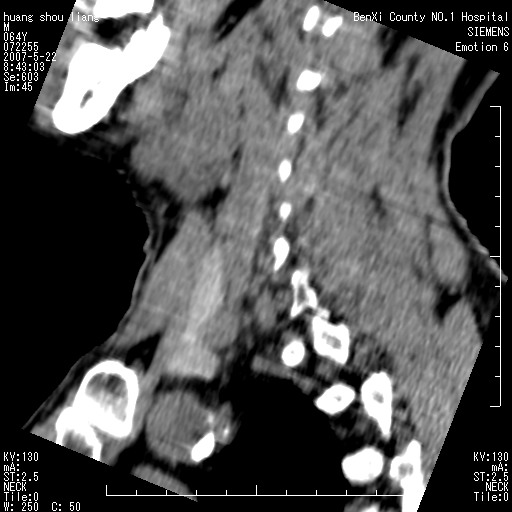

标题: CT8337:颈部包块8年,颈部CT和VRT,请讨论。

男性,64岁。颈部包块8年。最近增大。

对不起大家,可能是片子发太多有点乱,正常腮腺在下颌角的外侧,颌下腺在下颌体的中部内侧,本例在下颌角内侧偏下,和腺体一点关系都没有,从vrt和mpr上可以很明显看出来,再者肿块是好多粘连在一块的,大家在仔细看看,左侧可能也是吧,我还是考虑为肿大的淋巴结融合在一块,但性质??????

右侧腮腺下部均匀软组织密度肿块,外形不规则,与周围组织分界清晰,考虑右侧腮腺混合瘤或多形性腺瘤。

大家好,病理结果出来了,如大家所说,颌下腺混合瘤。

唉,解剖没学好吧,我诊断错了,不过还是有些不理解回去我在多看看书,谢谢大家的参与,以后我还会奉献好的病例。